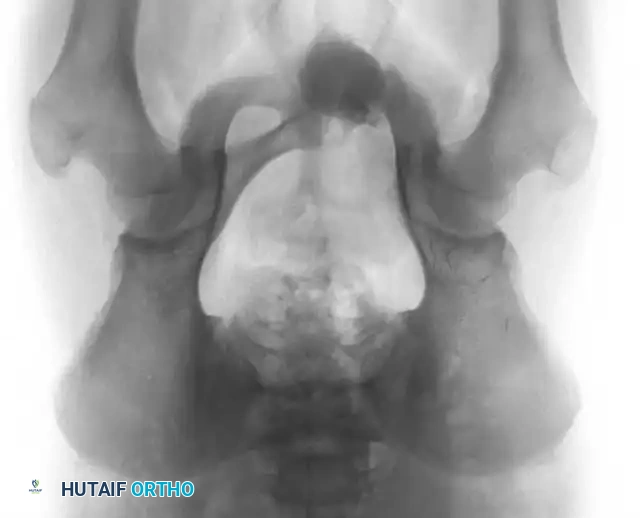

Fig. 20-22: (A and B) Pathological fracture of the right proximal tibia occurring through a large, expansile “brown tumor” of hyperparathyroidism in a 55-year-old woman.